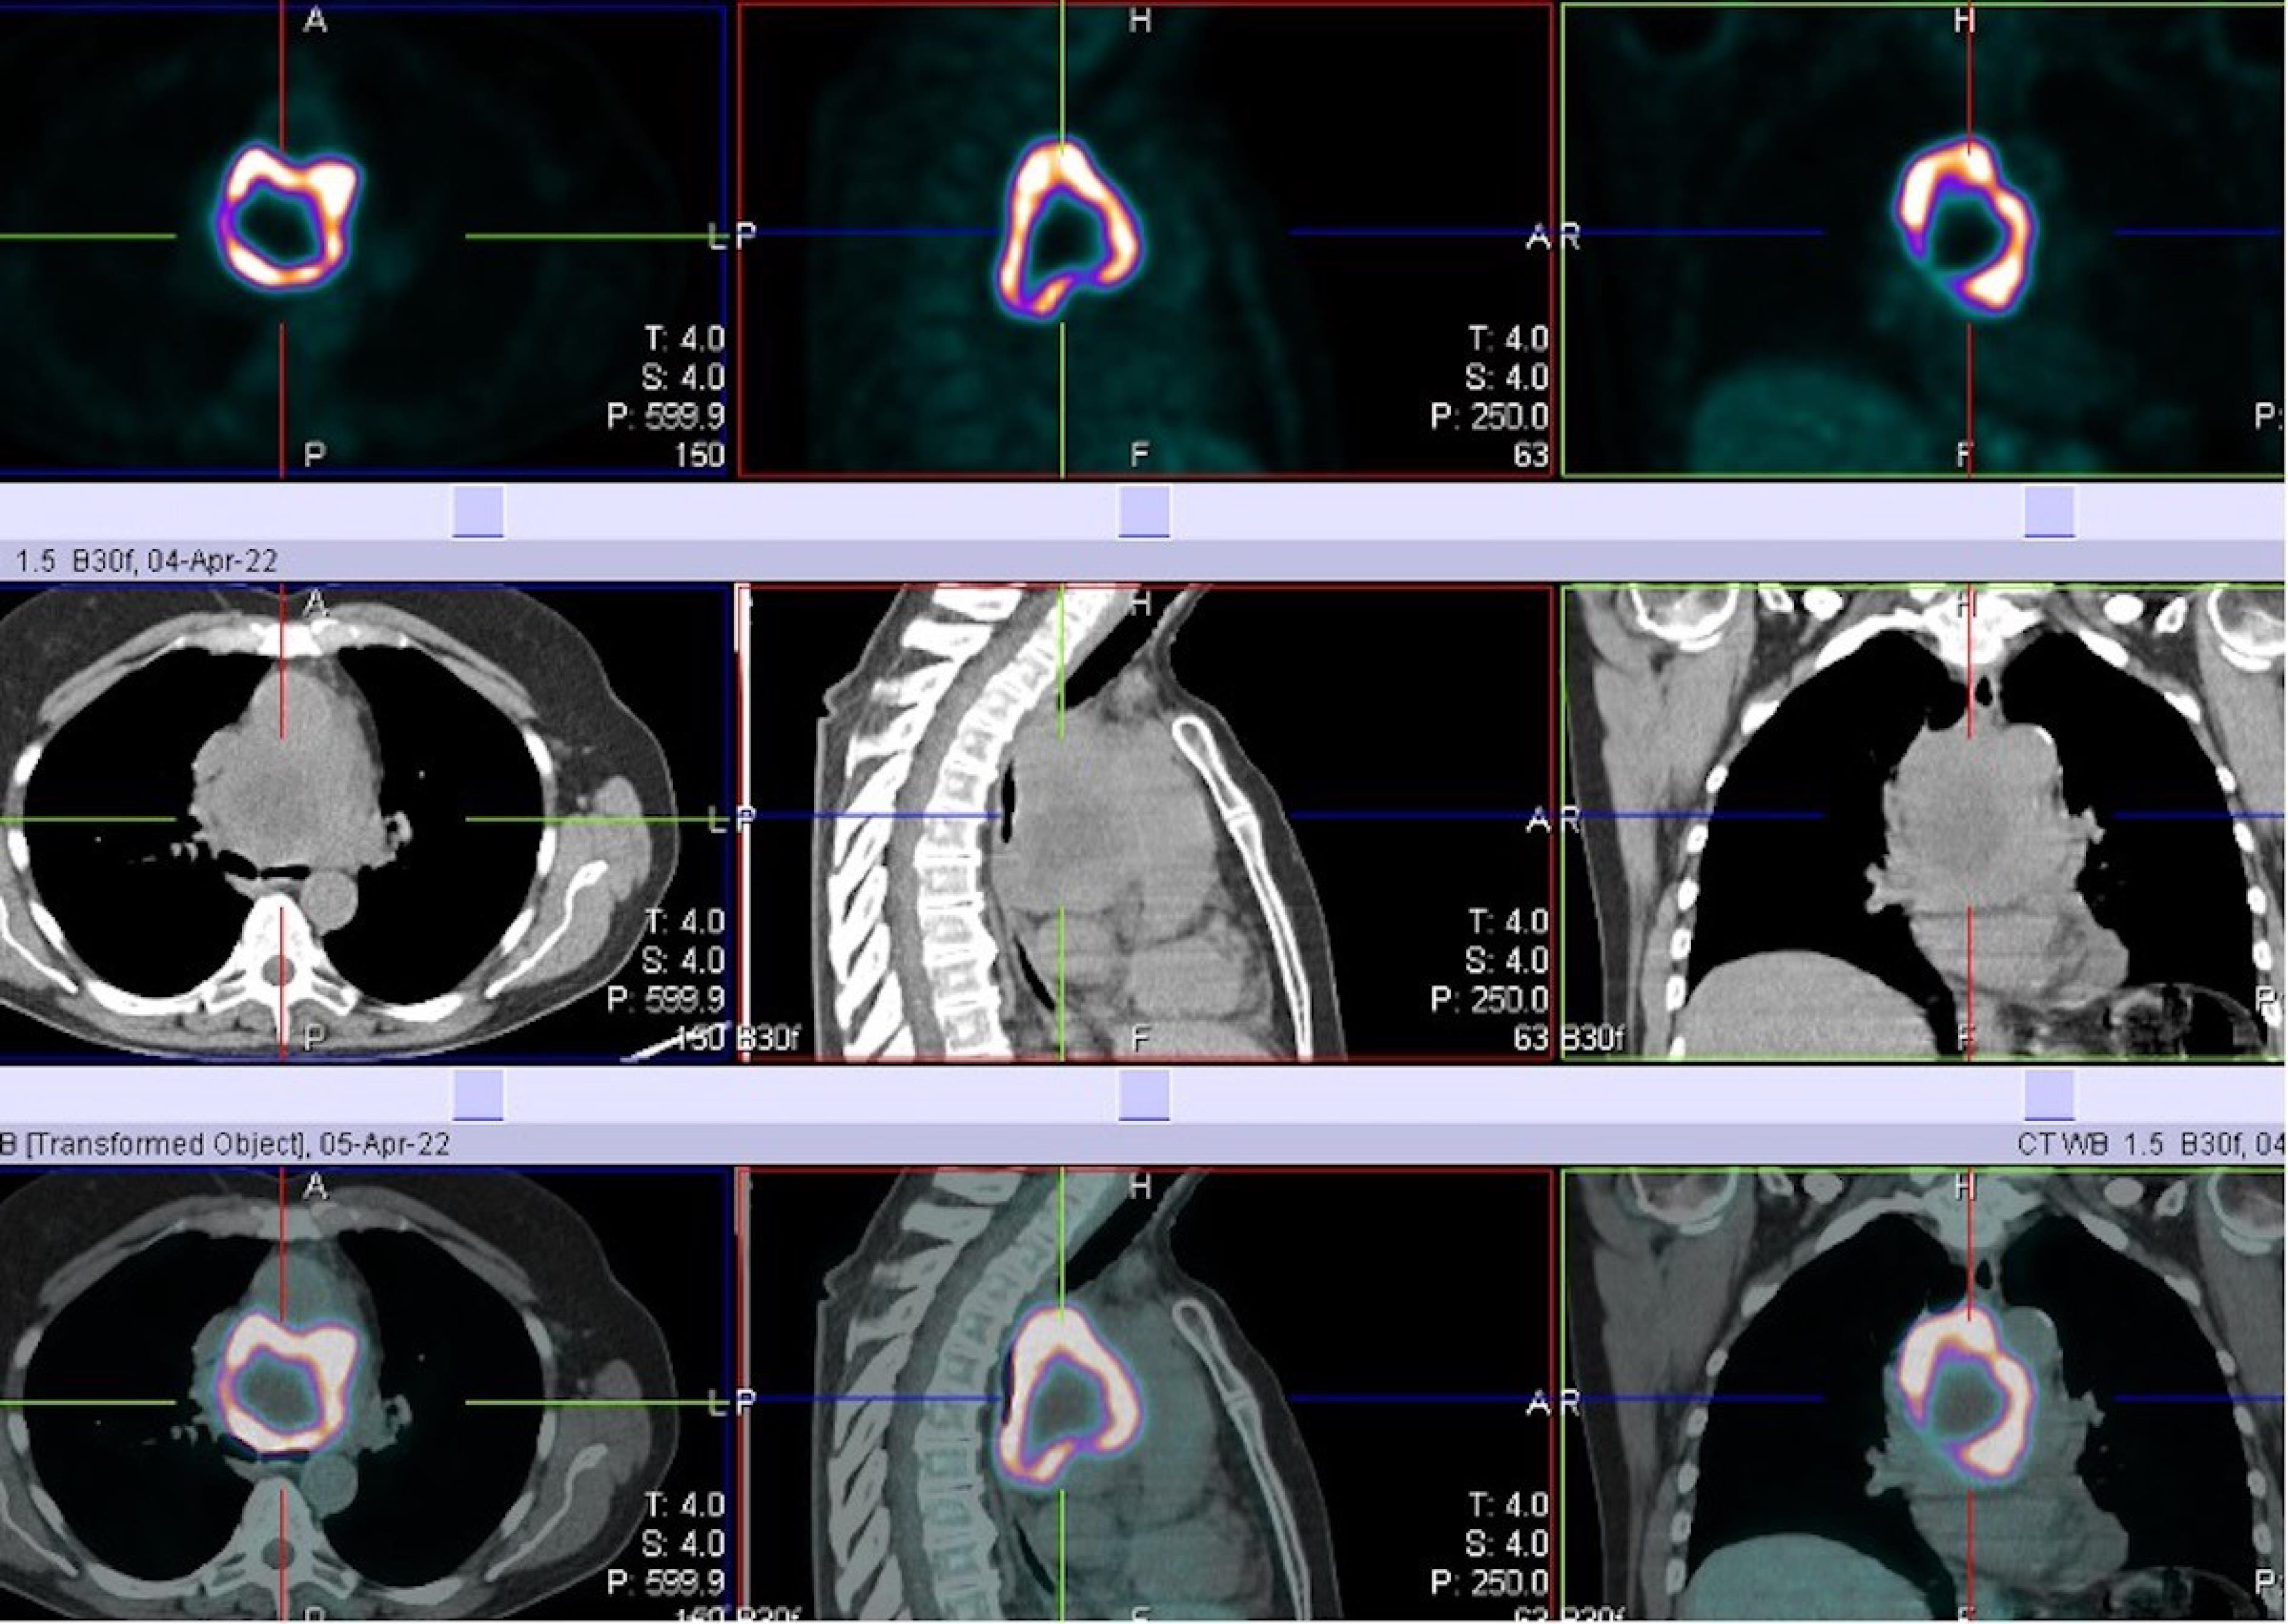

We report a case of a 67-year-old female who was incidentally diagnosed with a middle indeterminate mediastinal mass. Her past clinical history was characterized byarthritic symptoms as joint pain, loss of motion and inflammation. During follow-up, a Positron Emission Tomography (PET-scan) revealed a 9-cm middle mediastinal mass with a peripheral standardized uptake value (SUV = 20) with no evidence of extrathoracic uptake (Figure 1). A chest CT-scan revealed a large 70x60x30 mm well enhanced mass with necrotic central areas, located between the superior vena cava and the posterior portion of the ascending aorta, compressing the left atrium and, the trachea and main left bronchus posteriorly, surrounding the right pulmonary artery (Figure 2). A right uniportal video-thoracoscopic (U-VATS) biopsy of lesion was performed with a severe but controlled intraoperative bleeding. However, the mass remained undiagnosed so that a followed endobronchial-ultrasound transbronchial needle-aspiration (EBUS-TBNA), was suggestive of a paraganglioma. The patient was referred to surgery after multidisciplinary tumor board. A pre-operative coronarography revealed that the mass was perfused by a large tortuous vessel originating from the circumflex artery and smaller ones from the right coronary artery (Figure 3).

Figure 1.

Positron emission tomography combined with computed tomography scan (PET-CT) showing very intense uptake (SUV 20) at middle mediastinum of 9 cm in diameter mass with central no metabolic fluorodeoxyglucose (FDG) activity